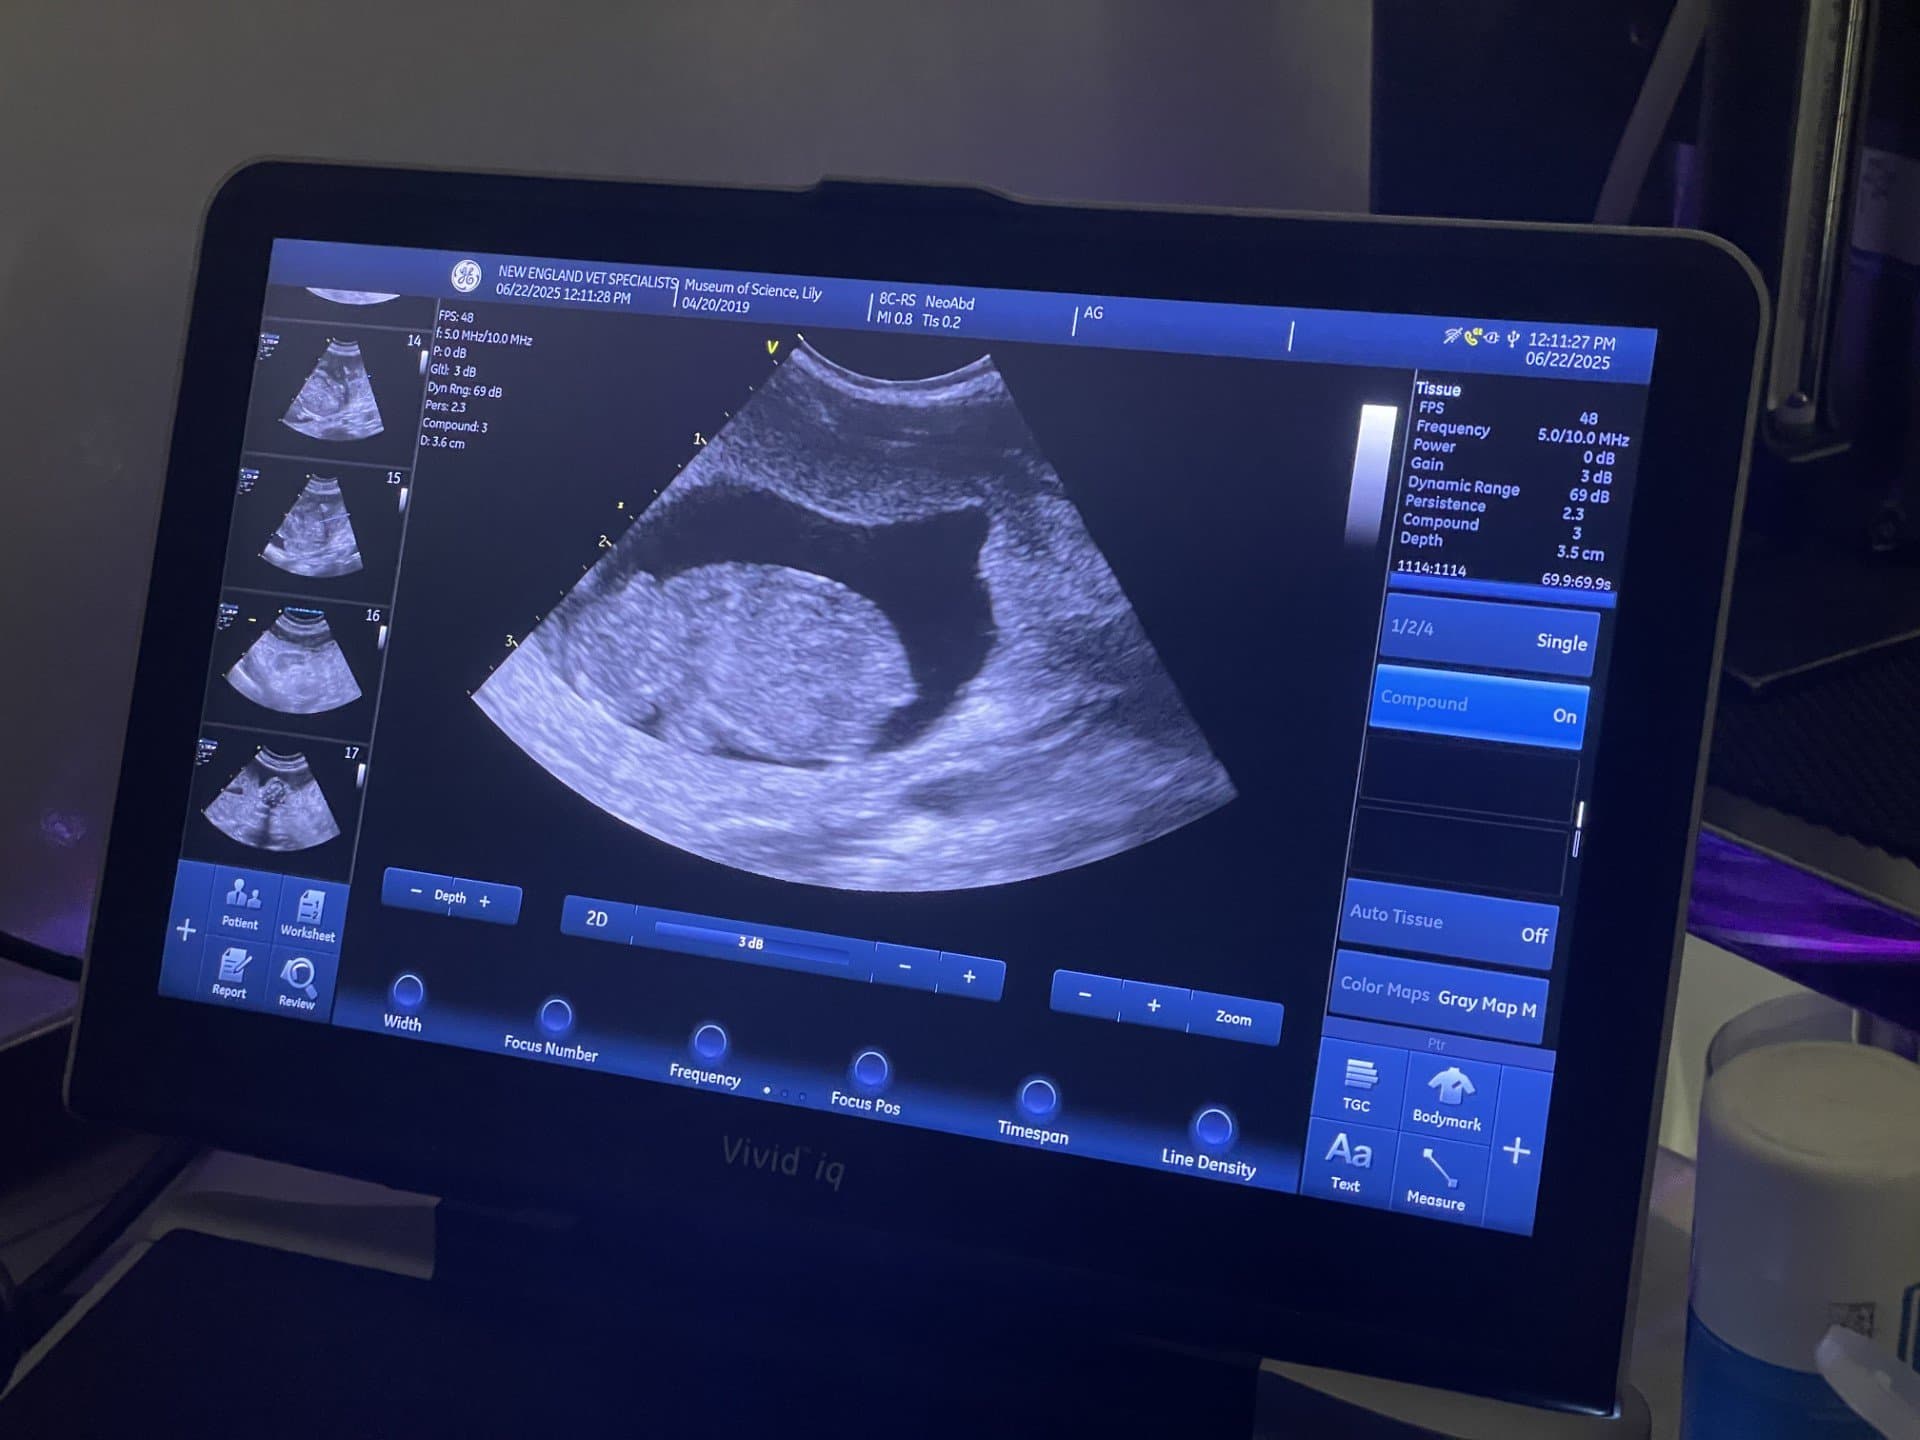

The Museum of Science participates in several SSPs, including cotton-top tamarins, radiated tortoises, lesser Madagascar hedgehog tenrecs, prehensile-tailed skinks, prehensile-tailed porcupines, and screaming hairy armadillos. Our armadillos are the only species we are currently breeding, and this summer we celebrated a success when we welcomed baby Backpack, the offspring of our long-term resident armadillos, Dora and Diego!